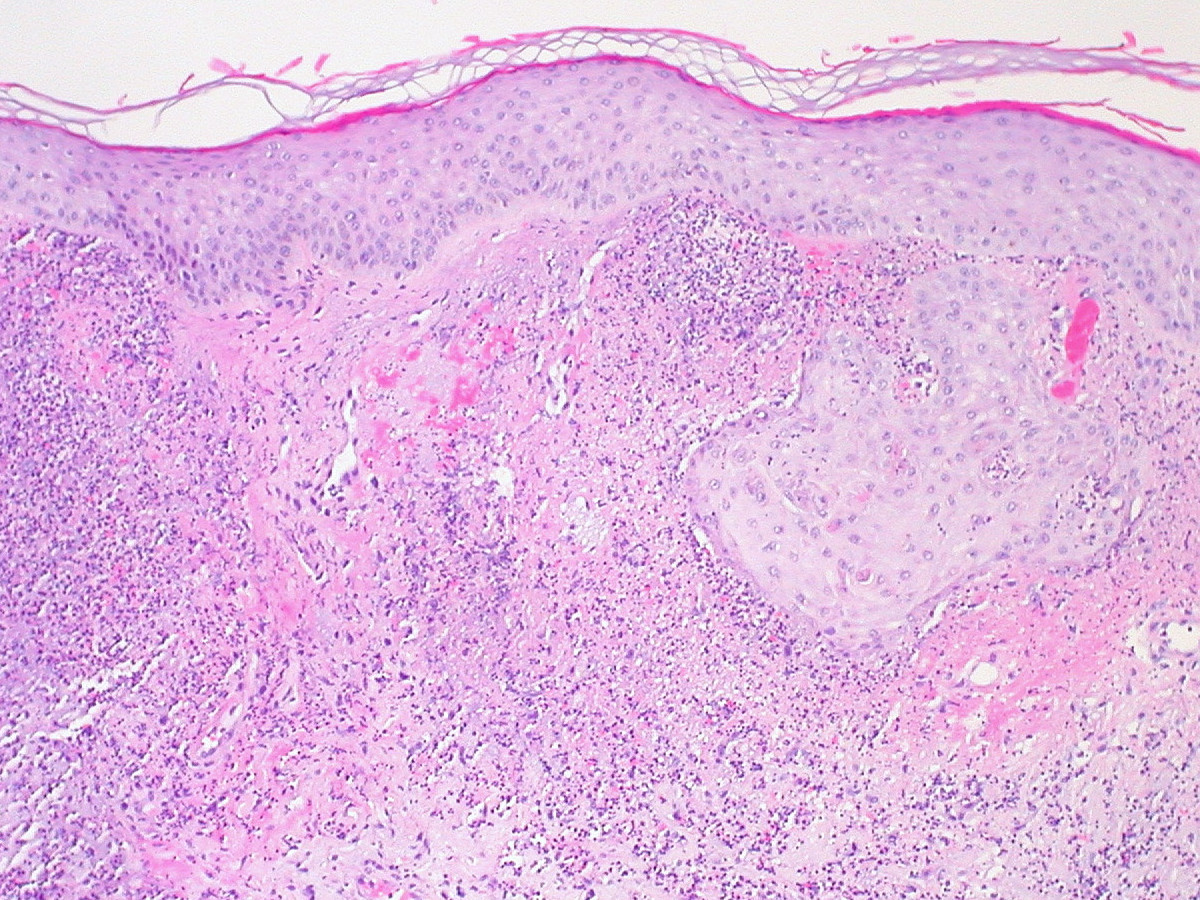

PA:Oedeem in de

papillaire dermis, een dicht leukocytair infiltraat, diffuus of perivasculair,

voornamelijk neutrofielen, soms eosinofiele of lymfoïde cellen. Gewoonlijk worden

vasodilatatie, erytrocyten-extravasatie en perivasculaire foci van leukocytoclasia

gezien welke een vasculitis suggereren, maar de vaatschade valt erg mee. De

epidermis is meestal normaal, zelden is er spongiose of exocytose, zelden subcorneale

pustels. Indien er neutrofielen in de epidermis aanwezig zijn, kan er sprake

zijn van subcorneale pustels. In dieper gelegen nodulaire lesies kan het infiltraat

beperkt zijn tot het subcutane vet. Soms worden subepidermale bullae gevormd.